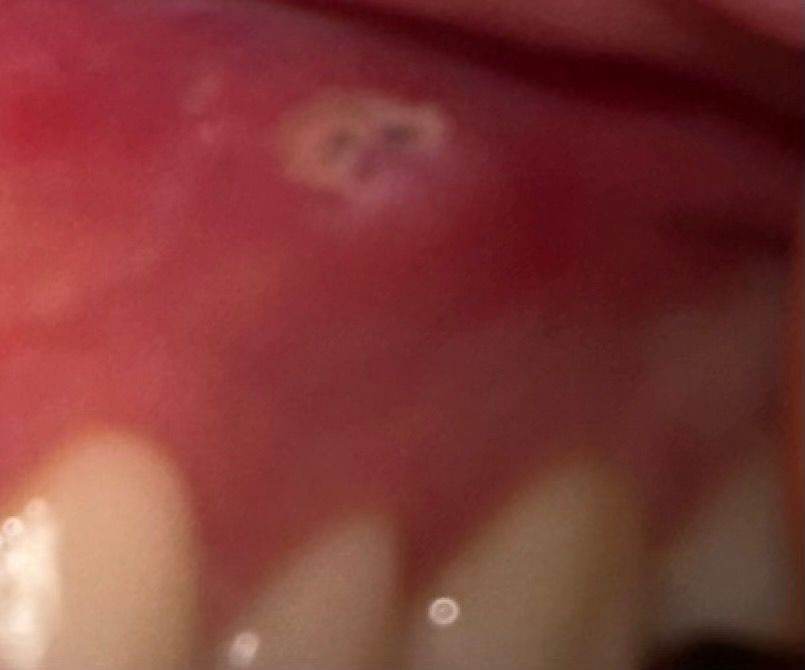

잇몸에 있는 이거 구내염이 맞는건가요?

잇몸에 뭔가 구내염 느낌이 들어서 알보칠을 바르고 어떤지 한번 거울로 봤는데 약간 검은 뭔가 있어서 구내염이 맞는지 잘 모르겠어요. 일단 바른 뒤에 최대한 잘 보이게 찍어봤는데 잇몸이 곪은건지 그냥 구내염인지 확인바랍니다.

• 2번 째 사진

현재 잇몸 상태를 보아서는 구내염이 아닌 치아 뿌리에 문제가 생겨 나타난 염증일 가능성이 큽니다. 잇몸 자체가 부어 있는 것으로 보아 sinus tract이 생겨서 치아 뿌리에 있는 염증이 바깥으로 나오면서 생긴 흔적으로 보여집니다. 정확한 판단을 위해서는 x-ray 등의 촬영이 필요할 것으로 보입니다. 너무 늦지 않게 치과 방문을 권해드립니다.

해당 부위 자극에 의해 발생한 궤양으로 추정되며 구내염의 일종으로 보입니다. 경과관찰 후 증상 개선 없을 시에는 정확한 평가 위해 구강악안면외과 또는 구강 내과 내원하시기를 바랍니다.